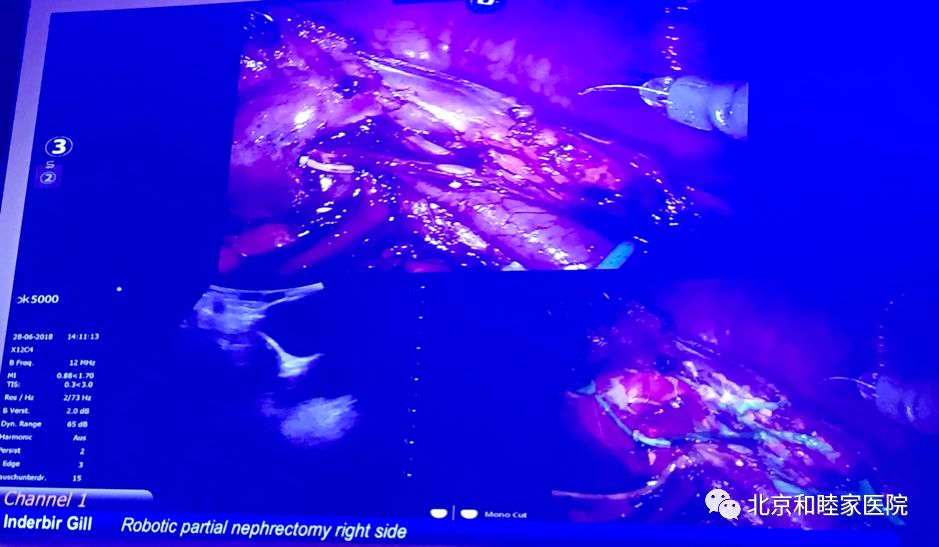

由于患者的原因,Inderbir Gill 没有进行计划的腔静脉癌栓取出术,而是做了一台右肾门下后方肿瘤的肾部分切除术。应该讲他的血管处理能力高超,经验丰富。在3D影像重建和3D打印的引导下,他十分娴熟地处理了3级血管,完整地实施了零缺血的肾下级切除术。当然,我们几位中国专家讨论认为他完全可以在肿瘤显露后仅实施肿瘤剜除,从而保留更多的正常肾组织。但无可否认,Gill显示的处理肾血管的高超技术和安全性,值得我们去学习。

Inderbir Gill应用机器人超声定位和3D影像重建导航进行手术